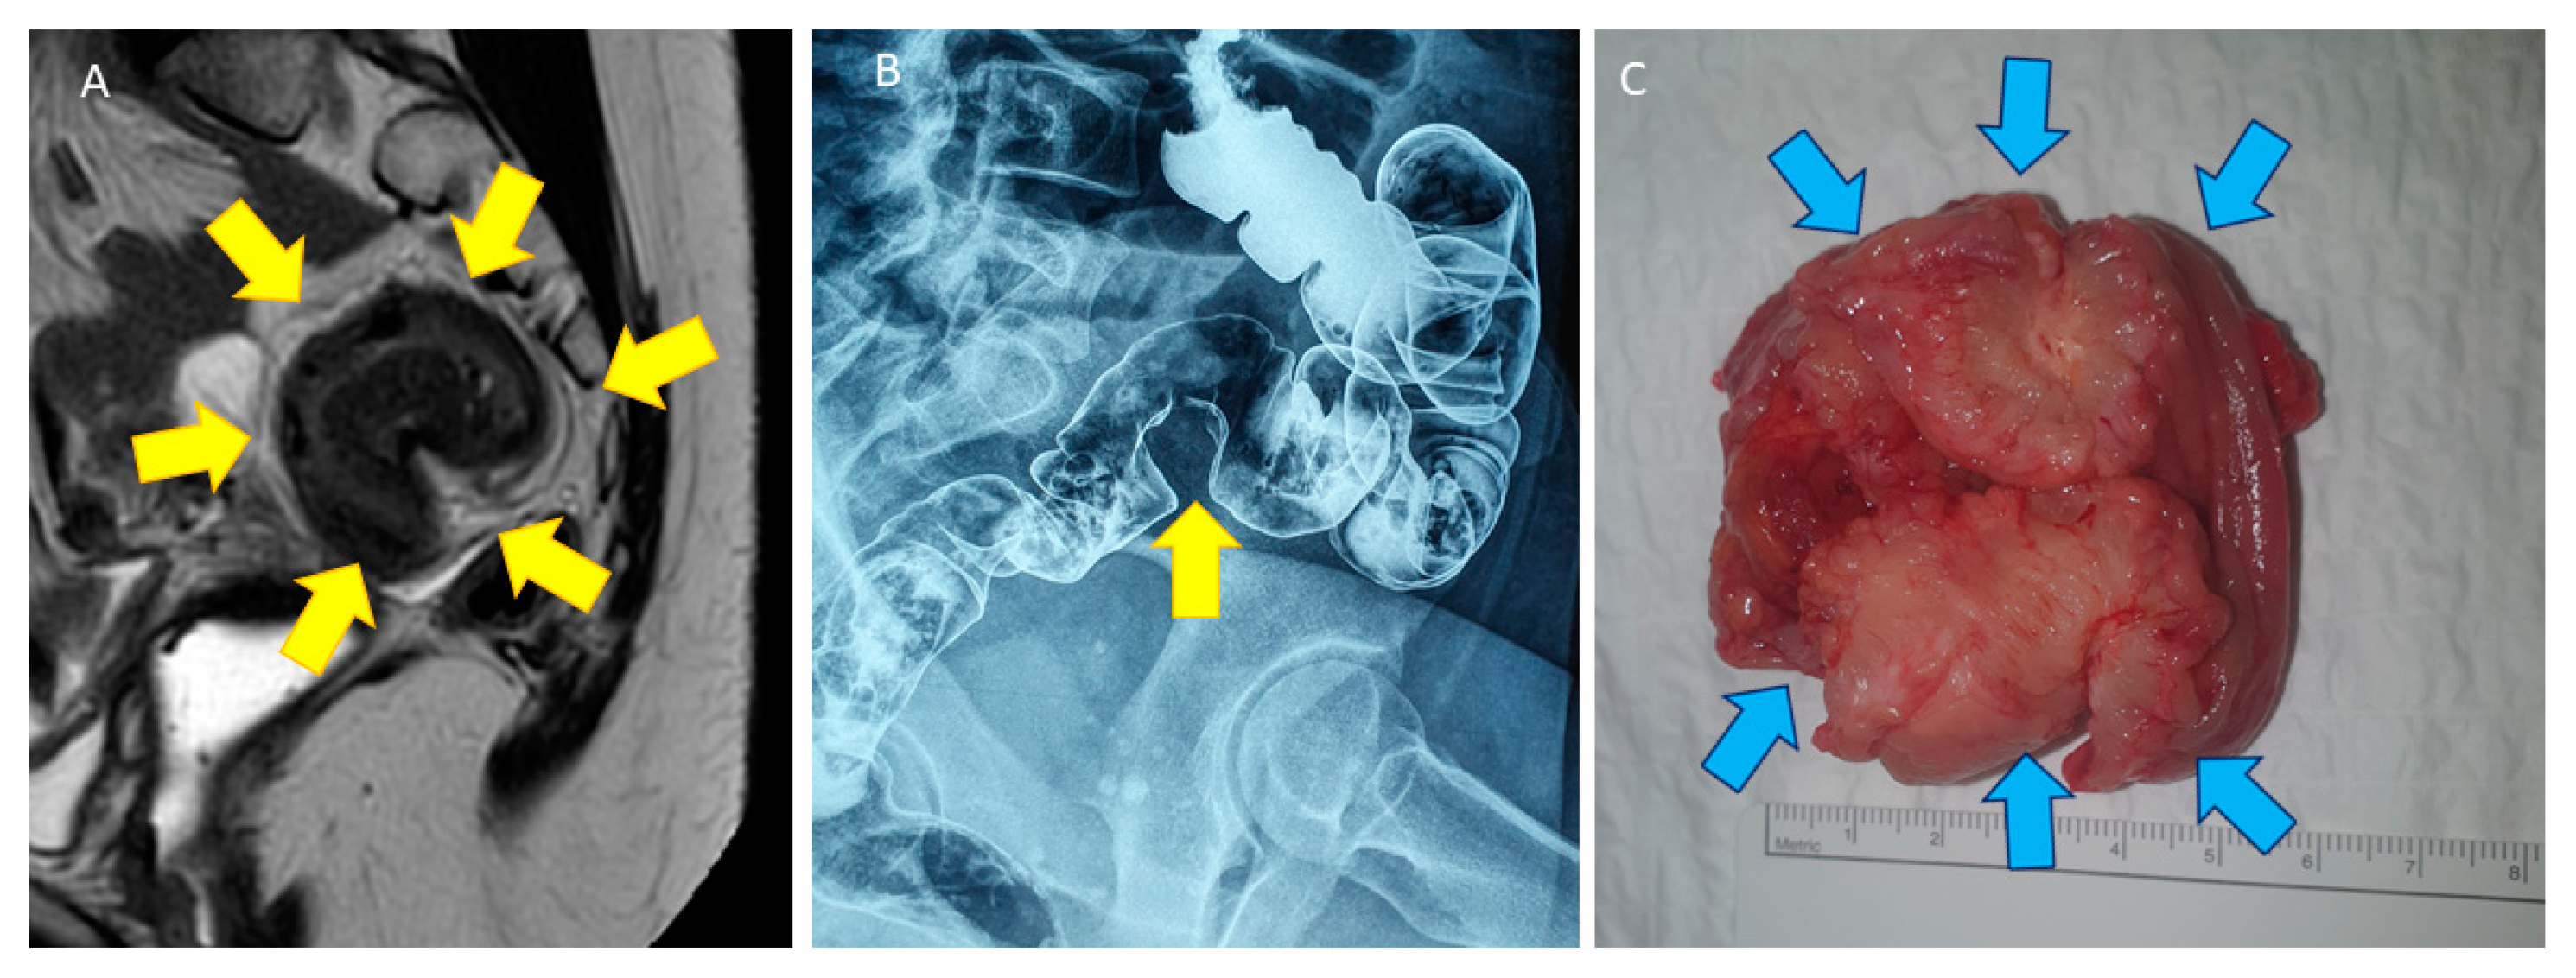

- Bazot, M.; Bharwani, N.; Huchon, C.; Kinkel, K.; Cunha, T.M.; Guerra, A.; Manganaro, L.; Buñesch, L.; Kido, A.; Togashi, K.; et al. European society of urogenital radiology (ESUR) guidelines: MR imaging of pelvic endometriosis. Eur. Radiol. 2017, 27, 2765–2775. [Google Scholar] [CrossRef]

- Jaramillo-Cardoso, A.; Shenoy-Bhangle, A.S.; VanBuren, W.M.; Schiappacasse, G.; Menias, C.O.; Mortele, K.J. Imaging of gastrointestinal endometriosis: What the radiologist should know. Abdom. Radiol. 2020, 45, 1694–1710. [Google Scholar] [CrossRef]

- Bazot, M.; Kermarrec, E.; Bendifallah, S.; Daraï, E. MRI of intestinal endometriosis. Best Pract. Res. Clin. Obstet. Gynaecol. 2021, 71, 51–63. [Google Scholar] [CrossRef] [PubMed]

- Biscaldi, E.; Barra, F.; Leone Roberti Maggiore, U.; Ferrero, S. Other imaging techniques: Double-contrast barium enema, endoscopic ultrasonography, multidetector CT enema, and computed tomography colonoscopy. Best Pract. Res. Clin. Obstet. Gynaecol. 2021, 71, 64–77. [Google Scholar] [CrossRef] [PubMed]